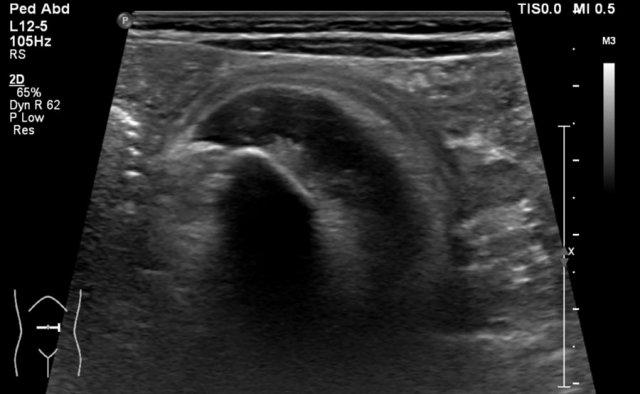

Video về một bé gái ba tuổi có khối u lớn ở hông phải.

Siêu âm với đầu dò tần số cao cho thấy khối u xuất phát từ thận phải.

The remnant of the collecting system is dilated.